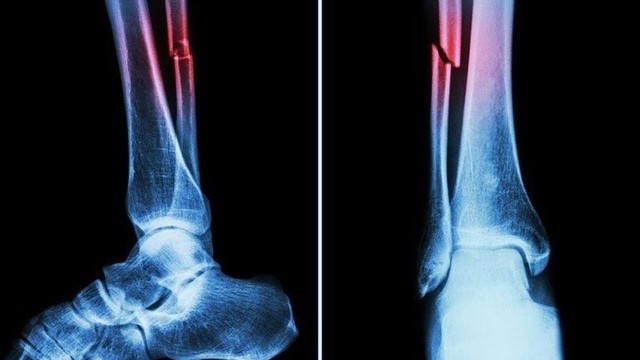

:format(webp)/gay_xuong_mac_co_da_bong_duoc_khong_4b0112d9be.jpg)

Gãy xương mác có đá bóng được không là thắc mắc của khá nhiều người đam mê sân cỏ sau khi mắc chấn thương. Hãy cùng Nhà Thuốc Long Châu tìm hiểu thời gian hồi phục sau gãy xương mác và lời khuyên nếu muốn đá bóng lại.